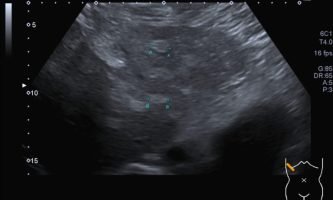

El médico de referencia le indica nueva ecografía de control, donde se observan múltiples y extensas lesiones focales hepáticas hiperecogénicas, redondeadas y confluentes, las cuales predominan en adyacencia a venas supra hepáticas, sin condicionar efecto de masa y sin alteración de la superficie hepática(fig. 1 y 2). Ante la valoración con Doppler color no presenta patrón de flujo peri ni intralesional y respeta el calibre de las venas supra hepáticas(fig. 3 y 4). Dada las características ecográficas se sospecha esteatosis focal multinodular confluente como principal diagnóstico presuntivo, siendo los diagnósticos diferenciales patologías de naturaleza infecciosa, tumoral o metastásica.

El examen radiológico abdominal más comúnmente utilizado en prevención es la ecografía (US) dado que es un método económico y accesible, no invasivo y que no utiliza rayos X, con el cual se logra fácilmente el diagnóstico de esteatosis, dado que se reconoce aumento difuso de ecogenicidad del parénquima hepático. Los criterios principales: la ecogenicidad del parénquima hepático debe ser mayor que la de la corteza renal, mala definición diafragmática, de los vasos supra hepáticos y de la arquitectura intra hepática.2(fig. 8, 9a y 9b)